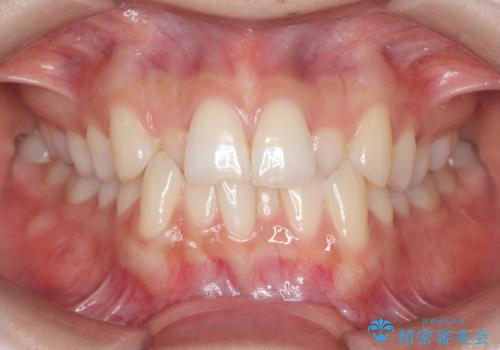

1年でここまで変わる。デコボコ歯並びの非抜歯矯正!

- 歯のデコボコ(叢生)を主訴にご来院された患者様です。

精密矯正検査を行った結果、歯を抜かずに行う、非抜歯のワイヤー矯正で治療を行う方針となりました。

歯並びの乱れに加え、**反対咬合(上下のかみ合わせのズレ)**も認められたため、見た目だけでなく、かみ合わせの改善も同時に行っています。

治療後は歯並び・かみ合わせともに大きく改善し、患者様にも大変ご満足いただけました。